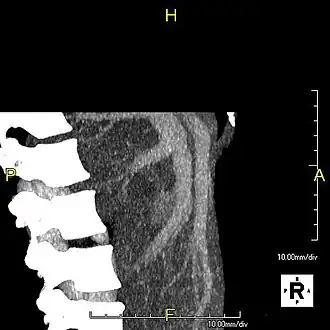

Lateral MIP view in the same patient as previous image -

A CT scan in which the liver and portal vein are shown